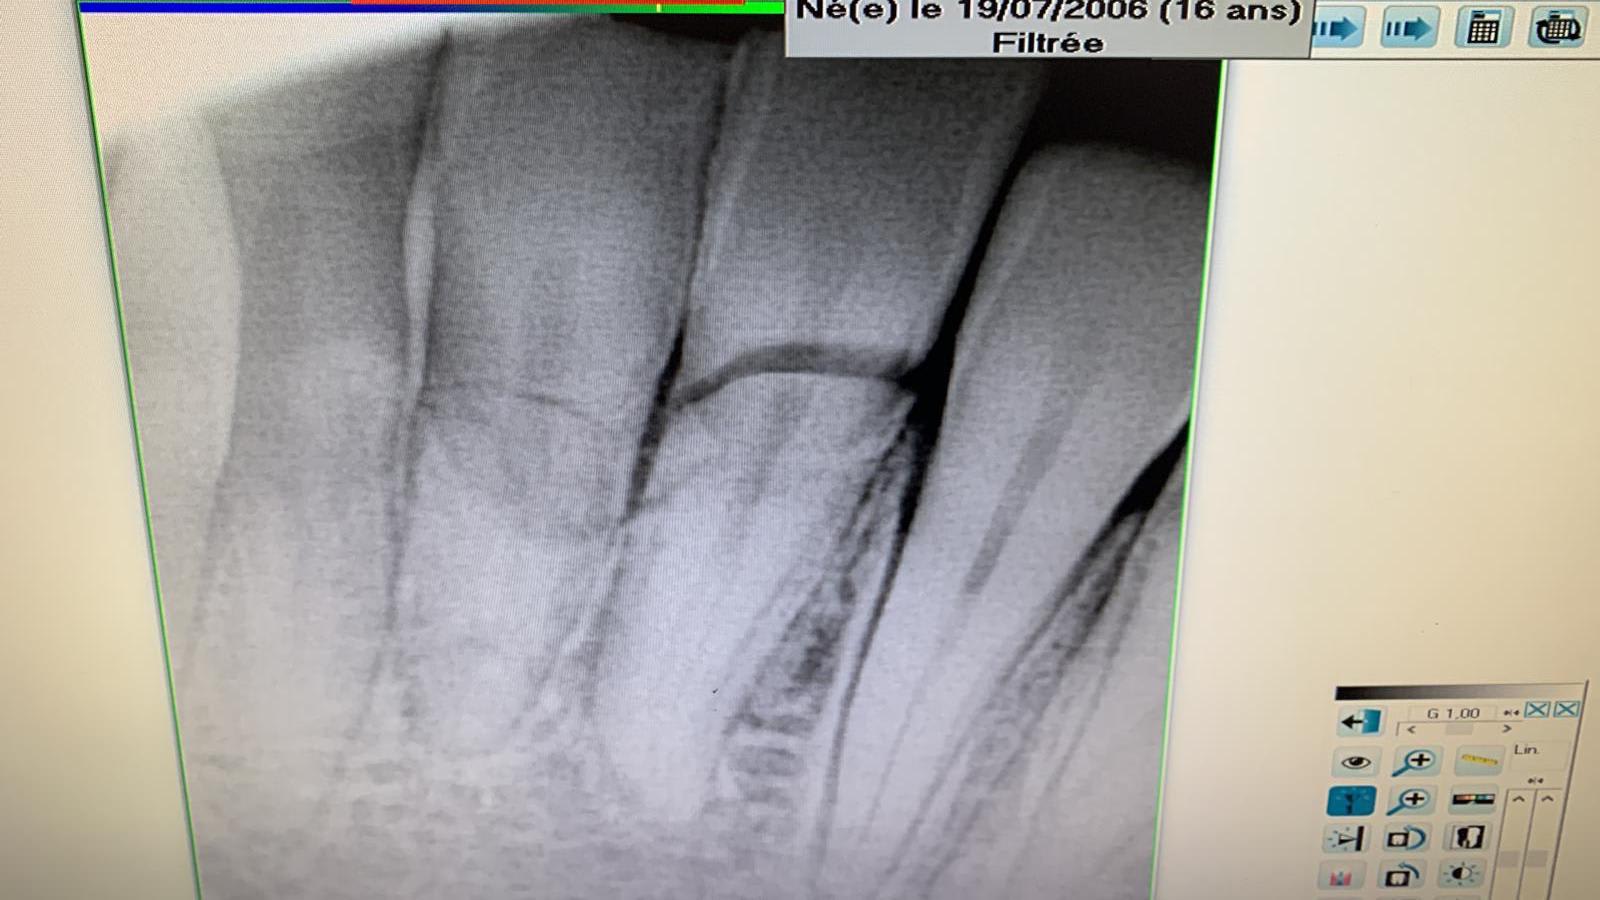

suite à une partie de foot, un gamin de 16 ans arrive avec 31,41 fracturées.

en urgence j'ai traité la 31, qui avait sa partie coronaire très mobile.

J'ai mis la photo pour que vous puissiez juger de l'ampleur de cette cassure.

extraction partie coronaire,dévitalisation,et remise en plan du pan fracturé avec pivot.

vu les radios il m’a dit qu’il y a pas de soucis